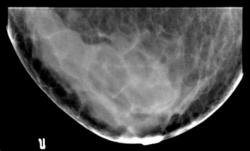

Протокол рентгенологического исследования. Общая скиалогическая картина инволютивной молочной железы. Преимущественно в верхнем наружном квадранте и центрально, в передних отделах молочных желез определяется нарушение структуры (архитектоники) молочной железы за счет снижения прозрачности, в результате субтотального избыточного развития соединительной ткани, на фоне чего определяются многочисленные тонкостенные кистозные образования средних и больших размеров. В верхнем внутреннем квадранте отдельные мелкие фиброаденомы

Заключение: Двусторонняя фиброзно-кистозная мастопатия.

Приводятся снимки одной левой молочной железы, так как скиалогическая картина правой железы почти зеркальна.

1. Левая молочная железа в прямой проекции (позитив).